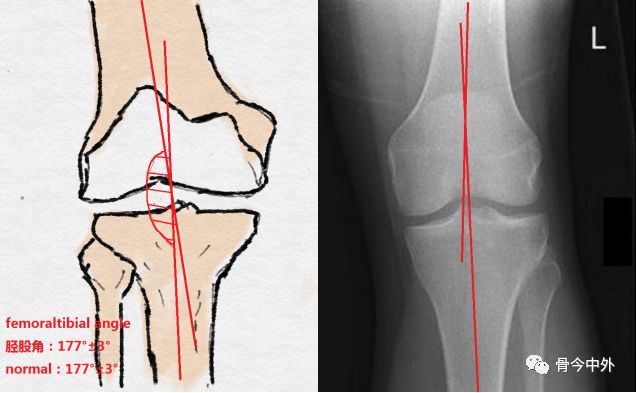

胫股角

胫骨机械轴线与股骨机械轴线的交角(正常:177°±3°)